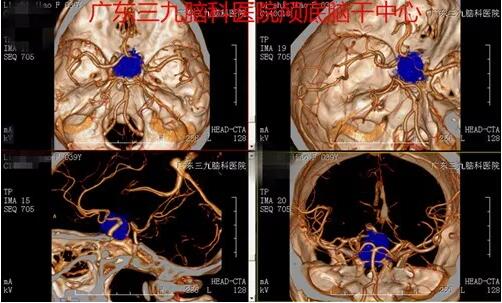

▲图1:术前CT示鞍区占位性病变,呈等、稍高混杂密度

▲图2:术前CTA示鞍内占位病变内未见明显血管影,考虑垂体瘤